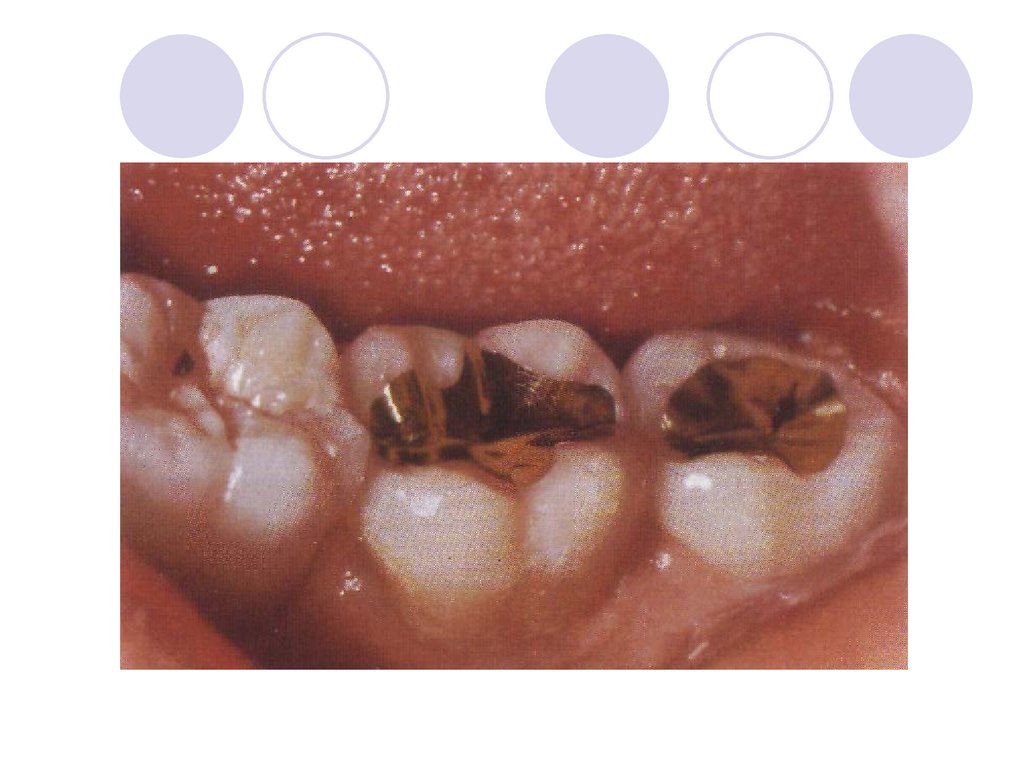

позволяет избежать ряда

Керамические вкладки

• Клинический случай: амал

-> плохо обработанная и

просушенная полость ->

краевой дефект -> поддесне

кариес в области контактн

поверхности.